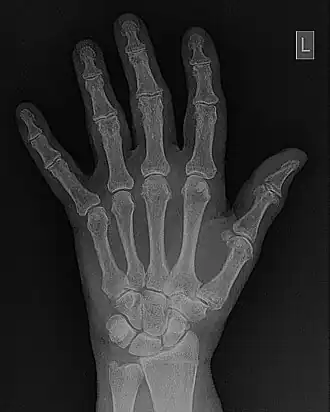

- Contrast enhancement can also be effected through manipulation of the image's statistical histogram and is illustrated in Figure 5.8. A histogram is a plot of the frequency of occurrence of each pixel value in an image - see panel (a) for an example, where this frequency is plotted as a function of pixel value. It can be seen that pixels from the black surroundings of the hand are indicated by the peak at low pixel values. It can also be seen that the pixel values representing bone and tissue attenuation form a broad range of lower frequencies extending to just over half the grey scale. Indeed the pixels of the 'L' marker can be seen to form an isolated blip at a pixel value of 75. Note that the term frequency as used here should not be confused with the term spatial frequency we have been using in our discussion of Fourier techniques.

DICOM-standard images contain what is called a header file which contains information regarding the patient, the examination and the image data - a section of one is shown in the following figure as an example. Note that in this case the image data refers to a hand/wrist image which is stored at a resolution of 2,920x2,920 pixels each of size 0.1 mm. In addition, default window display settings are shown. Furthermore, the form of image compression used can be included, i.e. whether lossless, which preserves the fidelity of image data, or lossy which degrades fidelity in the interest of image transfer speeds, for instance. Numerous other parameters can also be included in a header file.